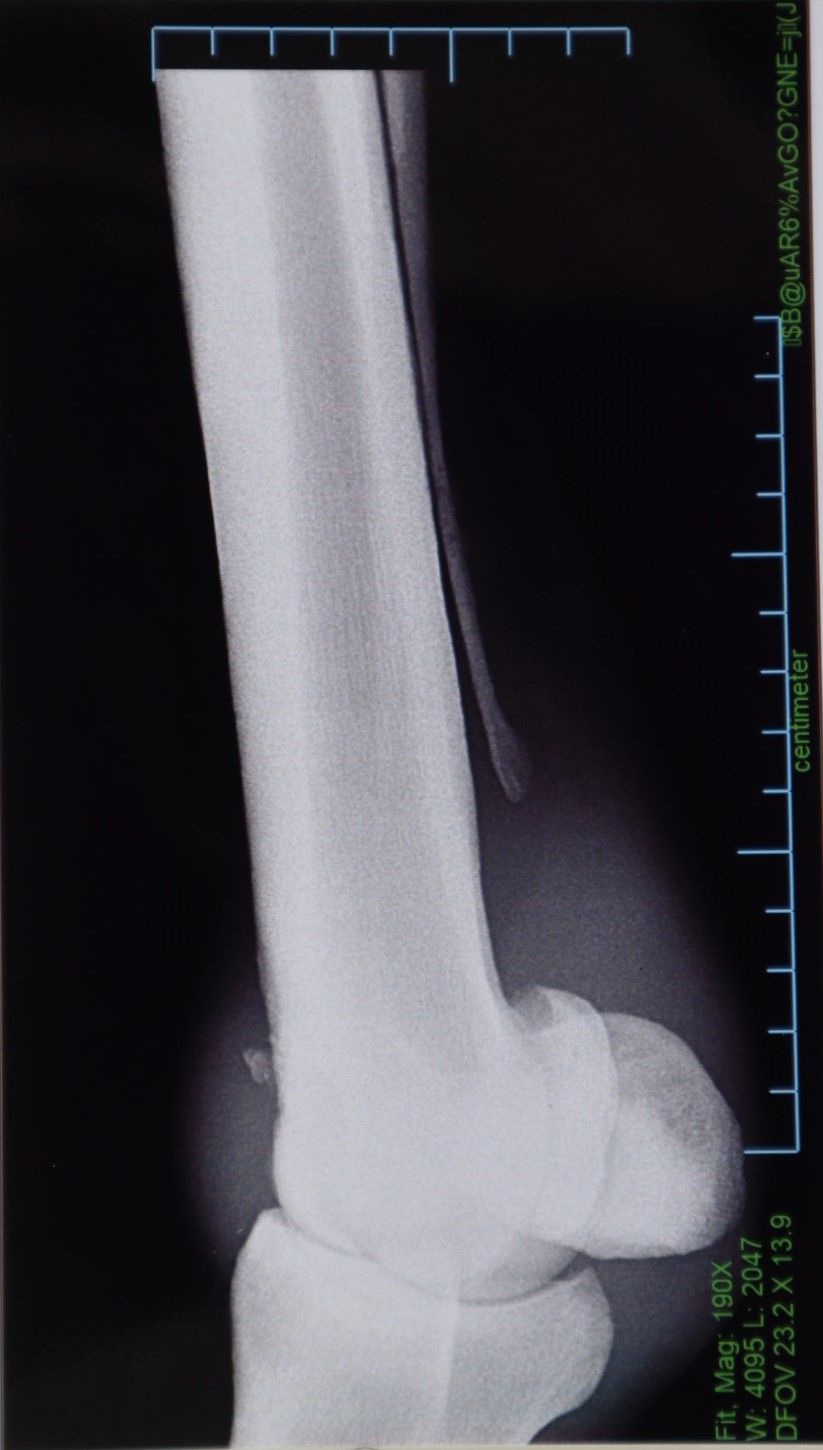

本馬は船橋・佐藤裕太厩舎より2歳9月にデビュー。2戦連続して2着となった後の3戦目に待望の初勝利を挙げます。ところが、両前の橈骨遠位端を剥離骨折するアクシデント。約1年に及ぶ長期休養に入ります。

今年に入っては心機一転、川崎競馬の現厩舎に移籍して実戦復帰。復帰3戦目に7勝目を挙げています。なお、今週の3回川崎開催(6/12~)での出走を目標にペースアップを図っていたところ、左前球節骨膜剥離が判明。残念ながら、今回の出品に至りました。

左前球節の骨膜剥離について『保存療法で対処できるレベルではあるものの、手術を行ってあげることに越したことはありません。いずれにしても、全治まで6~9ヵ月程度を要するでしょう』との診断を受けています。昨年、左前球節のトラブルで休養しており、その際の骨膜がこのタイミングではがれてしまったようです。前厩舎時代にも骨折した経緯があることを踏まえても、常に骨質の問題を抱えていたことでしょう。現B2クラスでも勝ち負けの目処が立ち、さらなる活躍が期待できていただけに残念です。(川崎競馬・鈴木義久調教師)

※2023年6月の調教中に左前球節骨膜剥離を発症しています。

※2019年12月11日(2歳時)の競走中に左前橈骨遠位端剥離骨折を発症。右前橈骨遠位端剥離骨折も判明したため、同月23日に両前の骨片摘出手術およびクリーニング手術を行っています。